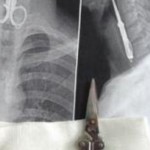

Αντιμέτωποι με ένα πρωτοφανές θέαμα βρέθηκαν οι ιατροί σε νοσοκομείο της ανατολικής Κίνας κοιτώντας τις ακτινογραφίες του 27χρονου Λιν Κονγκ. Βλέπετε, η εικόνα ενός ψαλιδιού μήκους εννέα και πλάτους τεσσάρων εκατοστών να κατεβαίνει στον οισοφάγο ενός ανθρώπου αν μη τι άλλο ξενίζει. «Όταν μπήκε στο νοσοκομείο, το πρόσωπό του ήταν χλωμό, ίδρωνε, δυσκολευόταν να καταπιεί και έφτυνε αίμα», λέει ο χειρουργός Τσεν Γουέι για τον ασθενή.

Όσο για τις συνθήκες του ατυχήματος, ο 27χρονος λέγεται πως έψαχνε για οδοντογλυφίδα αλλά δεν βρήκε. Ως εκ τούτου, αποφάσισε να σκαλίσει τα δόντια του με ένα… ψαλίδι.

Για κακή του τύχη, ωστόσο, ενώ σκάλιζε, κάποιος φίλος του είπε ένα ανέκδοτο με αποτέλεσμα αυτός να γελάσει και να καταπιεί το ψαλίδι το οποίο, τελικώς, χρειάστηκε ολόκληρη εγχείρηση για να αφαιρεθεί.